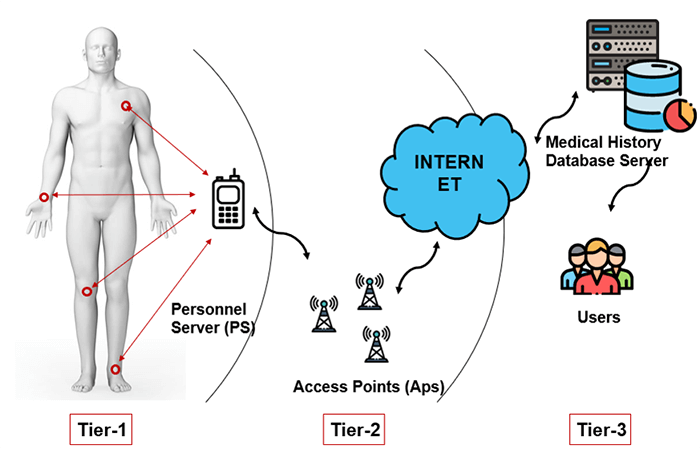

PACS requires controls that provide significant integrity, availability, and confidentiality assurances since it ties into doctor-patient workflow management. The results are based on image interpretation which aids in deciding a patient’s next step. These include the determination of health condition, follow-up visits, patient care, and other health-related actions. The three main tiers for possible confidentiality violations are Personnel servers, access points, and end-users.

Wireless Body Area Network (WBAN)

Wireless Body Area Network (WBAN) is a technique used for remotely monitoring the patient’s health and gathering the related information from the embodied sensors. It consists of a small wireless network that contains several small devices, i.e. sensor nodes and actuators. The sensor nodes are placed directly either on the body or under the skin of a person to compute certain body parameters such as an electrocardiogram (ECG), electroencephalogram (EEG), body movement, temperature, blood pressure, blood glucose, and respirations.

PDA

A smartphone can remotely access the information sensed by the sensors or a Personal Digital Assistant (PDA) between the patient and a doctor, nurses, pharmacies who take sensitive decisions or actions depending on the information acquired from those sensors. These critical decisions and medical information must be protected against unauthorized access that could be dangerous to the life of the patient and sometimes lead to death, i.e. change of dosage of drugs or treatment procedures, if falls on the wrong hand. Thus, scalable and strict security mechanisms are mandatory and should include secure group management, confidentiality, privacy, integrity, authorization, and authentication.